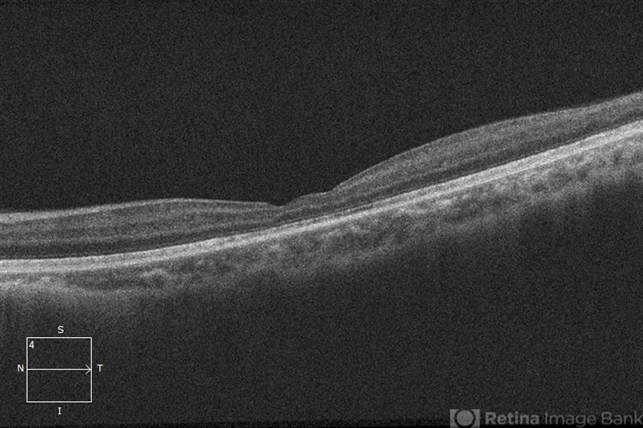

- retinoschisis, retinal hole

- Imaging device

Optical coherence tomography system

Zeiss Cirrus 5000 - Description

- 21-year-old male with congenital retinoschisis with bilateral macular involvement and large inner retinal hole OD. Foveoschisis collapsed OS, since last exam in 07/2015.